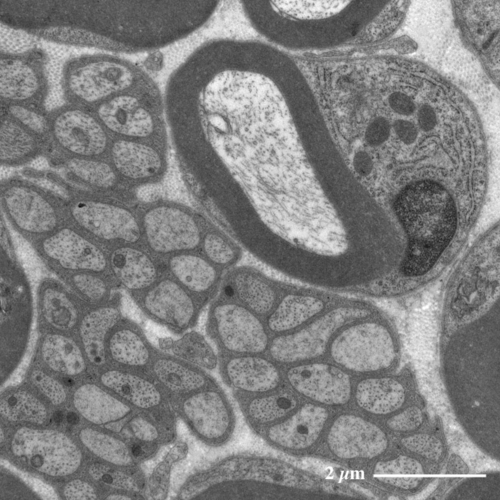

坐骨神経(ラット) Sciatic nerve ( rat )

【 薄さ70 - 80 nm 超薄切片の透過型電子顕微鏡画像 】

Transmission electron microscopic image of 70 - 80 nm ultrathin section

有髄神経(右上)と無髄神経(左下)の電子顕微鏡像

有髄神経の髄鞘を取り巻くシュワン細胞(*)